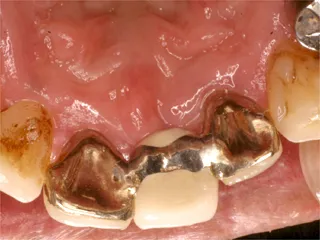

| 保険ブリッジ |

保険ブリッジ・頬側

■長所 ・安い ■短所 ・前後の歯を削り犠牲にする ※前後の歯を削り被せものをします ※抜けた歯のかわりに金属が付いています |